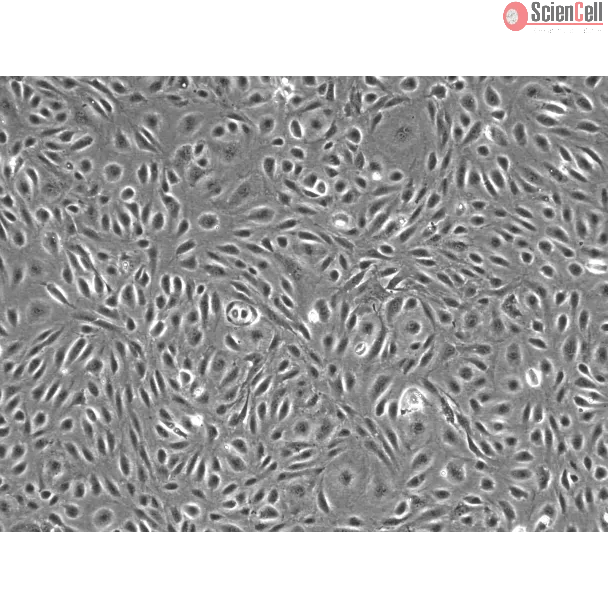

Human Dural Microvascular Endothelial Cells

Isolated from human dura mater. HDuMEC are cryopreserved at passage one and delivered frozen. Each vial contains >5 x 105 cells in 1 ml volume.